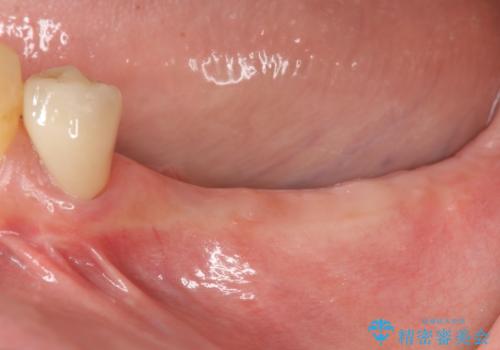

過大な咬合力で破折した奥歯 インプラント治療で咬合機能の回復